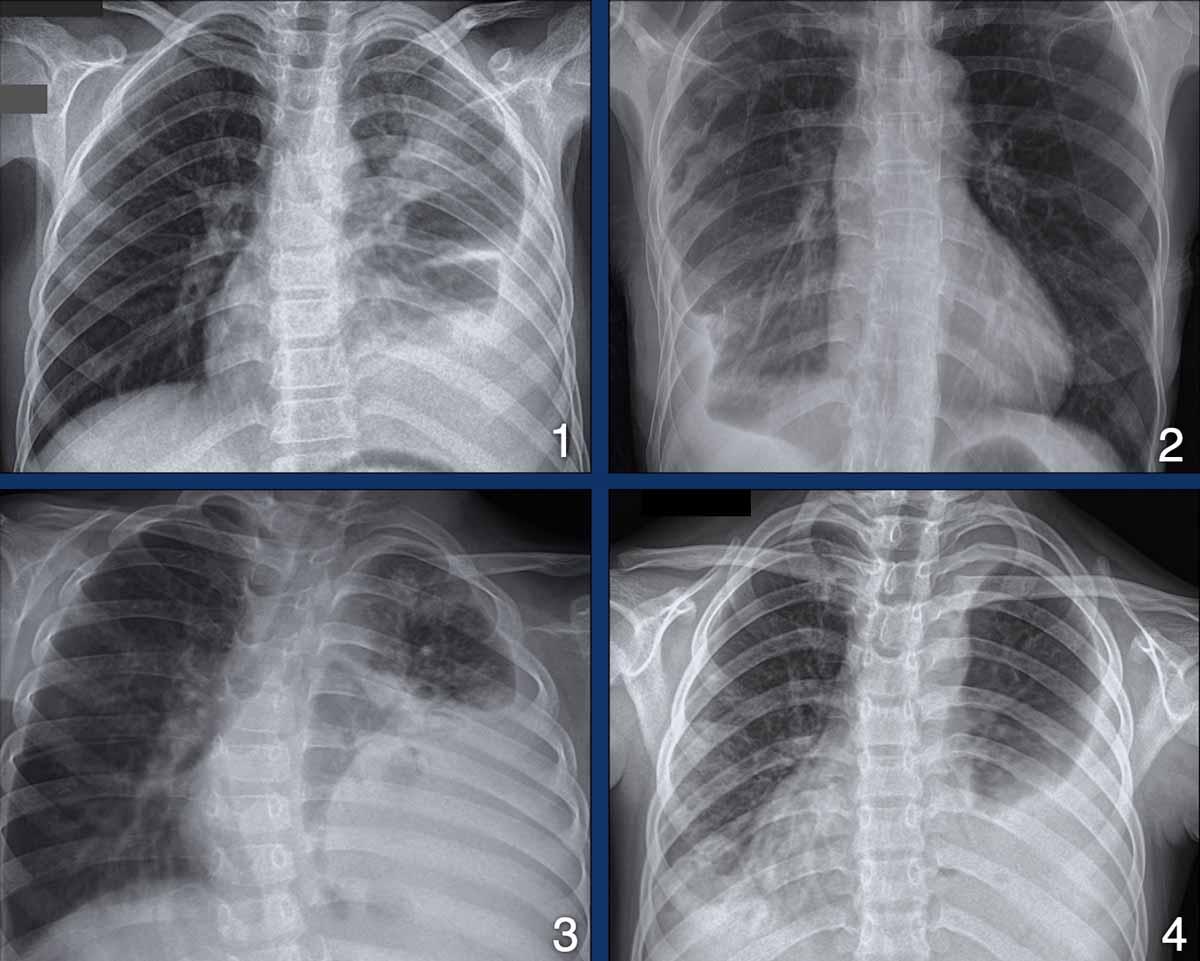

Các hình ảnh cho thấy bốn ví dụ về tràn dịch màng phổi ở bệnh nhân lao.

Hình ảnh

- Bé trai 12 tuổi với biểu hiện mệt mỏi, sụt cân và ho mạn tính.

Có đông đặc thùy trên trái và lượng lớn tràn dịch màng phổi. - Tràn dịch màng phổi một bên. Lưu ý cũng có bất thường xương sườn. Đây có thể là kết quả của lao.

- Lượng lớn tràn dịch màng phổi gây lệch trung thất và chèn ép phổi trái ở bé trai 6 tuổi.

- Lượng lớn tràn dịch màng phổi cả phía dưới và phía trên phổi trái bị xẹp.